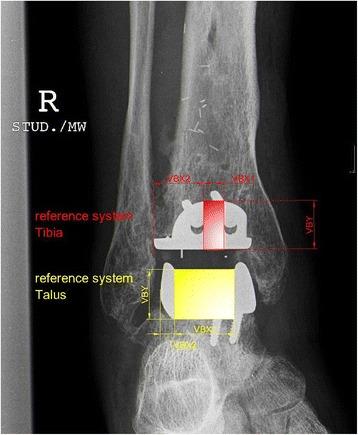

The rotational position of the leg substantially influences measurements in ankle radiographs after total ankle replacement (TAR). The aim of our study was to further specify the influence of different projections on radiographic parameters used to assess component position after TAR.

The effect of varying degrees of internal rotation, flexion, and ab-/adduction on reference lines in anteroposterior and lateral ankle radiographs was investigated in a cadaveric TAR model. Observed variations were then compared with those found in 34 consecutive patients that received a HINTEGRA total ankle prosthesis in our department.

A change of rotation of 20° resulted in a variation of measured reference lines of more than 1.3 cm in anteroposterior radiographs and more than 1 cm in lateral radiographs in our experimental setting. Even higher intraindividual changes of up to 1.4 cm were observed in our in vivo series.